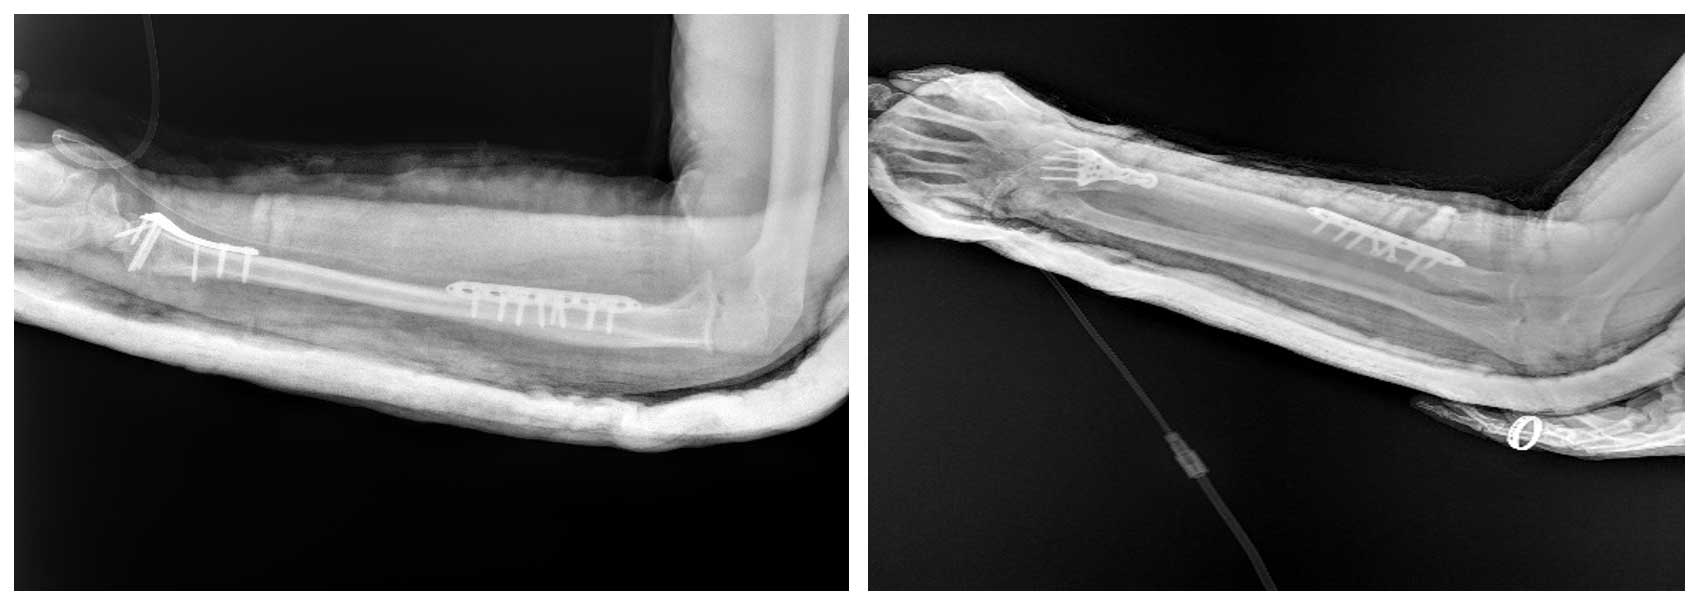

Görsel Açıklamaları

Ameliyat Öncesi: Röntgende radius distalde düzensizlik ve skleroz, MR’da çevreleyen yumuşak doku komponenti görülmekte.

Ameliyat Sonrası: Röntgende geri kazanılan kemiğin proksimal ve distalde plak ile fiksasyonu görülmekte.